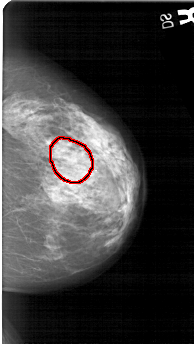

FILE: A_1322_1.RIGHT_MLO.OVERLAY

TOTAL_ABNORMALITIES 1

ABNORMALITY 1

LESION_TYPE MASS SHAPE ROUND MARGINS CIRCUMSCRIBED

ASSESSMENT 4

SUBTLETY 2

PATHOLOGY BENIGN

TOTAL_OUTLINES 1

BOUNDARY